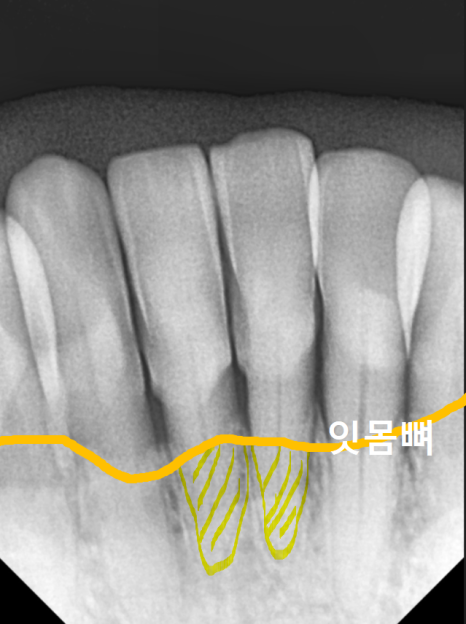

결국 이 환자분은 치석이

잇몸뼈를 너무 많이 녹여,

방사선 사진상 뿌리 끝만

뼈에 간신히 걸쳐 있었습니다.

흔들림이 너무 심해

치아를 살리기 어려운 단계였기에,

결국 아래 앞니 2개(#31, 41)를 발치하고

임플란트를 하기로 결정했는데요.